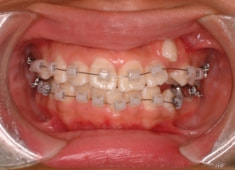

治療後(1年12ヶ月後)